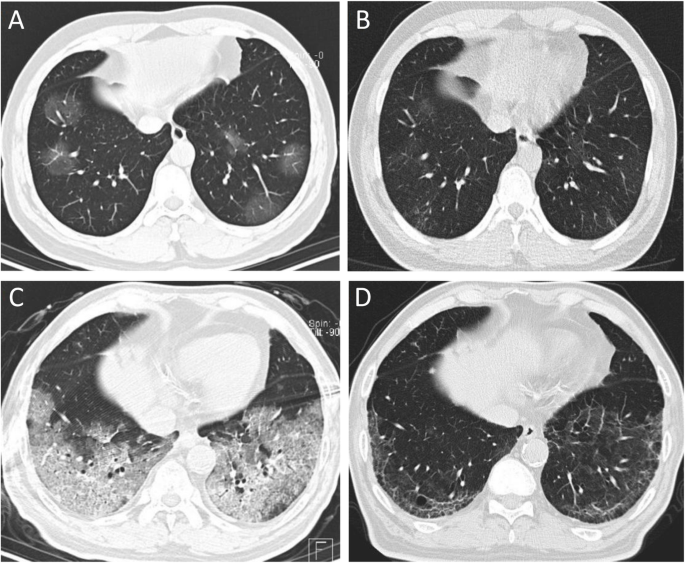

Several full cases are reviewed, and the basic principle behind a scoring system is discussed. In an image sequence, the infection points may appear in some images and not be shown. Limited supply of vaccines now available for eligible populations at select cvs pharmacy stores.

The diagnostic value of high resolution computerized tomography (hrct) scan chest in corona virus disease 2019. Most commonly was ggo that accounted for 120(88.9%). Ct has a higher sensitivity but lower specificity and can play a role in the diagnosis and treatment of the disease. Several full cases are reviewed, and the basic principle behind a scoring system is discussed.